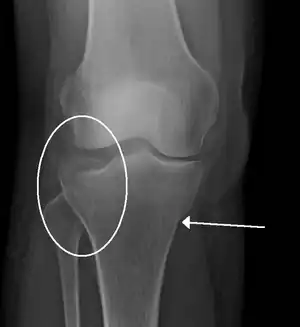

| A tibial plateau fracture | |

- Tibial plateau fracture

- Bumper fracture - a fracture of the lateral tibial plateau caused by a forced valgus applied to the knee

- Segond fracture - an avulsion fracture of the lateral tibial condyle